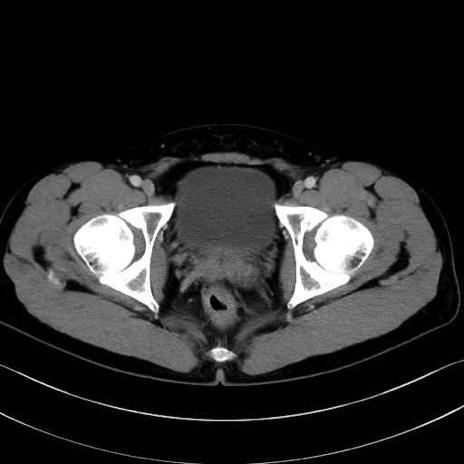

恥骨筋(pubic muscle) のCT画像の解剖

恥骨筋 (Pectineus)

長内転筋 (Adductor longus)